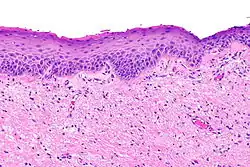

Paraqueratosis

En medicina y dermatología, el término paraqueratosis se utiliza para describir una alteración en el proceso de queratinización de la piel, en la cual desaparece el estrato granuloso y los núcleos celulares son visibles en el estrato córneo. En circunstancias normales, el estrato córneo de la epidermis está formado por células planas queratinizadas y carentes de núcleo. La presencia de paraqueratosis es normal en el epitelio de la boca y otras mucosas. En la piel se observa en diferentes enfermedades, entre ellas la psoriasis. No debe confundirse con la poroqueratosis que es otro entidad dermatológica diferente.[1][2][3]